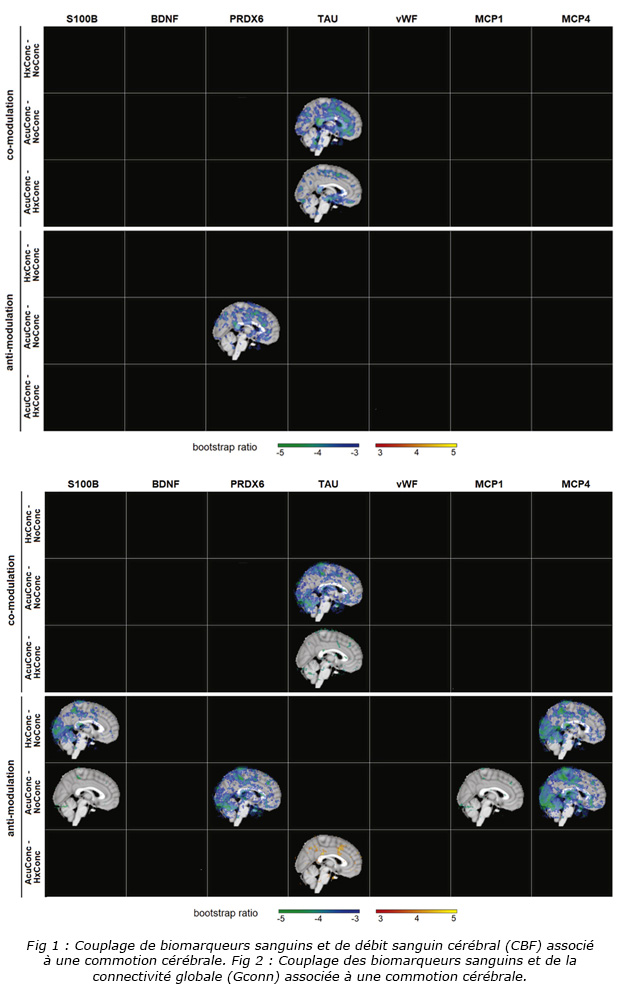

Par rapport aux athlètes en bonne santé, les athlètes récemment commotionnés ont présenté des modifications concomitantes plus importantes de plusieurs biomarqueurs sanguins périphériques et mesures de l’IRM : diminution de la FCP avec PRDX-6 élevé et diminution de Gconn avec MCP-4 élevé. Les associations entre la CBF et les biomarqueurs sanguins sont illustrées à la Fig. 1. En outre, par rapport aux athlètes en bonne santé sans antécédents de commotion, les athlètes en bonne santé ayant déjà subi une commotion cérébrale ont présenté des altérations concomitantes plus importantes des biomarqueurs sanguins et de Gconn ; GConn inférieure coïncide avec des taux sanguins plus élevés de s100B et de MCP-4. Les associations entre les biomarqueurs Gconn et sanguins sont illustrées à la Fig. 2.

Afin de mieux interpréter le schéma spatial des effets de commotion cérébrale observé pour CBF (Fig. 1) et Gconn (Fig. 2), la Fig. 3 ci-dessous illustre des cartes par voxels comptant le nombre d'analyses de biomarqueurs cérébraux ayant détecté des effets de commotion importants.

Les régions du cerveau où le couplage avec des biomarqueurs sanguins est associé de la manière la plus fiable aux effets de commotion cérébrale. Les cartes en couleurs illustrent le nombre d'analyses dans lesquelles les voxels montrent un effet de commotion cérébrale important pour le flux sanguin cérébral (CBF) sur la base des résultats de la Fig. 1 et pour la connectivité fonctionnelle globale (Gconn) sur la base des résultats de la Fig. 2.

Les différentes modalités d'imagerie fonctionnelle utilisées dans cette étude, y compris l'ASL et l'IRMf à l'état de repos, fournissent des informations complémentaires sur les réponses neurophysiologiques possibles liées aux biomarqueurs sanguins après SRC. Sur la base des distributions spatiales rapportées (Fig. 3), les résultats indiquent que la SRC est principalement associée à la covariance de biomarqueurs sanguins et de CBF fronto-temporaux. Les résultats concordent avec le fait que ces régions de matière grise sont vulnérables aux blessures primaires causées par des impacts à la tête, des études antérieures de neuro-imagerie montrant des effets fronto-temporaux associés à la fois à une blessure aiguë et à des antécédents de commotion. Inversement, les analyses de Gconn ont montré le plus grand couplage cerveau-biomarqueur dans les régions occipito-pariétales.

Par conséquent, les effets des lésions neurologiques sur la connectivité fonctionnelle concernent principalement les zones associées à la fonction visuelle et à l’orientation visuo-spatiale. Ces résultats sont également cohérents avec des études antérieures qui ont rapporté des effets de commotion cérébrale sur la connectivité fonctionnelle au repos dans les régions occipitales et pariétales.

Les différentes modalités d'imagerie fonctionnelle utilisées dans cette étude, y compris l'ASL et l'IRMf à l'état de repos, fournissent des informations complémentaires sur les réponses neurophysiologiques possibles liées aux biomarqueurs sanguins après SRC. Sur la base des distributions spatiales rapportées (Fig. 3), les résultats indiquent que la SRC est principalement associée à la covariance de biomarqueurs sanguins et de CBF fronto-temporaux. Les résultats concordent avec le fait que ces régions de matière grise sont vulnérables aux blessures primaires causées par des impacts à la tête, des études antérieures de neuro-imagerie montrant des effets fronto-temporaux associés à la fois à une blessure aiguë et à des antécédents de commotion. Inversement, les analyses de Gconn ont montré le plus grand couplage cerveau-biomarqueur dans les régions occipito-pariétales.

Par conséquent, les effets des lésions neurologiques sur la connectivité fonctionnelle concernent principalement les zones associées à la fonction visuelle et à l’orientation visuo-spatiale. Ces résultats sont également cohérents avec des études antérieures qui ont rapporté des effets de commotion cérébrale sur la connectivité fonctionnelle au repos dans les régions occipitales et pariétales.